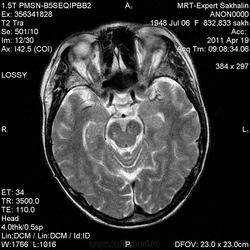

склоняюсь к кровизлиянию в левой теменной долей, начало перехода острой стадии в раннюю подострую( по периферии определяется повышение МРС по Т1 ВИ -метгемоглобин). Справа -старые кортикальные постишемческие глиозно-атрофические изменения. Контрастируется , вероятно за счет формирования участков ангионеогенза.

Это демиелинизирующий процесс, острая стадия, причем с геморрагическим пропитыванием в центре пораженных участков. В принципе, соответствует тяжелому рассеяному склерозу, хотя может быть и геморрагическая форма ОДЭМ. Также могут быть мозговые проявления системного васкулита: надо знать анамнез.

На фоне ДЭП изменений МР-картина ОНМК по ишемическому типу в бассейне ЛСМА с участками геморрагического пропитывания. Аналогичный участок но в более поздней фазе в задних конвнкситальных отделах правой теменной доли.

О.С., я согласен, что контрастирование нехарактерно для ОНМК, ведь в подострую стадию инфаркта наблюдается, как правило, гиральный тип усиления. Плюс, на ОНМК непохоже то, что поражено почти только белое вещество, а кора интактна. И потом, при такой локализации инфаркта обязательно должна быть яркая клиника, и уж никак не только "головная боль".

Что касается снимочков мне кажется что зона патологического сигнала в левой гемисфере можно расценить как подострую стадию ОНМК с геморрагическим пропитыванием, справа как последствия ОНМК. При чем множественные очаги скорей всего как проявление ХМНК. И обязательно рекомендовать контрольное МРТ в динамике . Если это действительно ОНМК на фоне лечения отек уйдет и будет формированиться зона кистозно-глиозных изменений, а если отек будет нарастать значит надо думать о объемном процессе.

ОНМК по геморрагическому типу, почти классика.